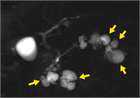

1. IPMNとは膵管内に乳頭状に発育し、多量の粘液を産生、膵管拡張を来す疾患である。主膵管型と分枝膵管型に分類され、主膵管型では主膵管のびまん性拡張像、分枝膵管型では分枝膵管の嚢胞状拡張像(ブドウの房状)が特徴である。